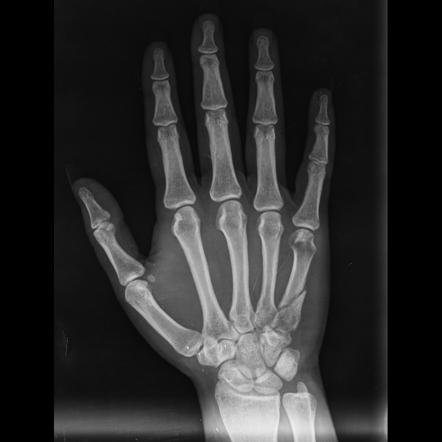

Fractures of the metacarpal bones, the long bones of the hand connecting the fingers to the wrist, are common injuries often caused by falls, sports activities, or direct trauma. In recent years, significant advancements in medical technology have led to the development of metacarpal locking plates, revolutionizing the treatment of hand fractures. These innovative implants have shown pro

mising results in providing better stability, faster healing, and improved patient outcomes compared to traditional treatment methods. In this article, we explore the benefits and surgical techniques associated with metacarpal locking plates, along with the advancements that have further enhanced their efficacy.

Metacarpal fractures can vary in severity and location, affecting different parts of the hand. They are commonly classified into several types, including:

Metacarpal locking plates represent a major breakthrough in the treatment of hand fractures. These plates are specially designed to provide stable fixation and support during the healing process.